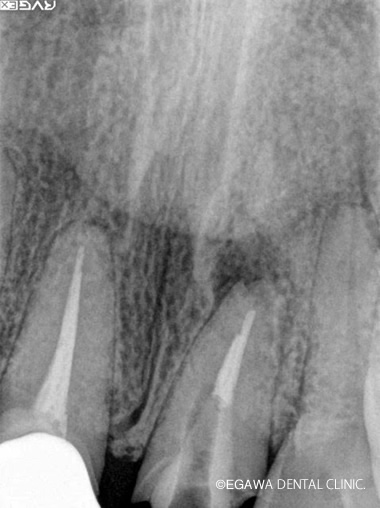

先端に病巣がありますが、歯根端切除とMTAセメントによる逆根管充填により病巣が治癒しています。

症例1

術前

術中

術後